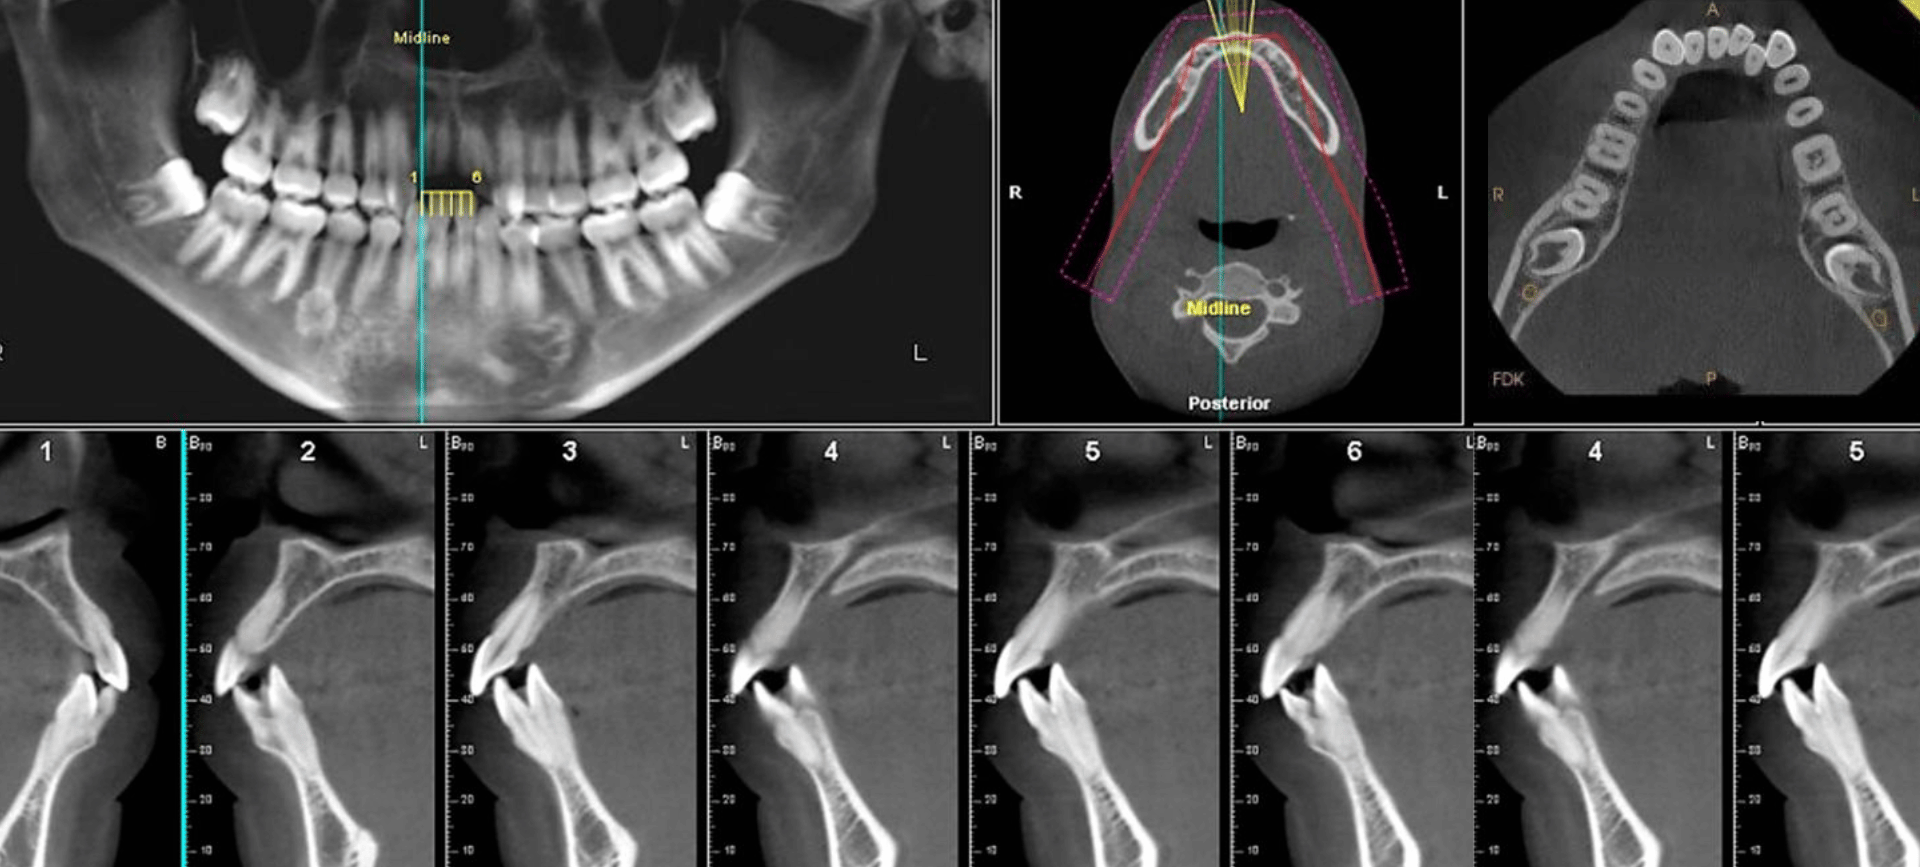

Dr. Sukhjinder Kaur Gill is an experienced Oral & Maxillofacial Radiologist with over 16 years of expertise in dental and maxillofacial imaging, including CBCT, OPG, Lateral Cephalograms, and advanced 3D diagnostics.

Holding a BDS and MDS in Oral Medicine and Radiology, along with specialized training in CBCT interpretation, tele-radiology, and AI-assisted diagnostics, she leads Wave Imaging LLP—a network of modern imaging centers across Pune (FC Road, Aundh, Kothrud, Wakad, Kharadi, Baner).Wave Imaging stands out for:

– High-resolution, low-radiation CBCT scans

– Same-day reporting and digital delivery

– Patient-friendly, stress-free experienceUnder her guidance, the team delivers precise, actionable reports to support dentists, implantologists, orthodontists, oral surgeons, and ENT specialists—bridging advanced technology with compassionate care.“Precision imaging turns diagnostics into confident treatment and smiles.”For reliable CBCT support in Pune, connect with Dr. Gill and Wave Imaging.